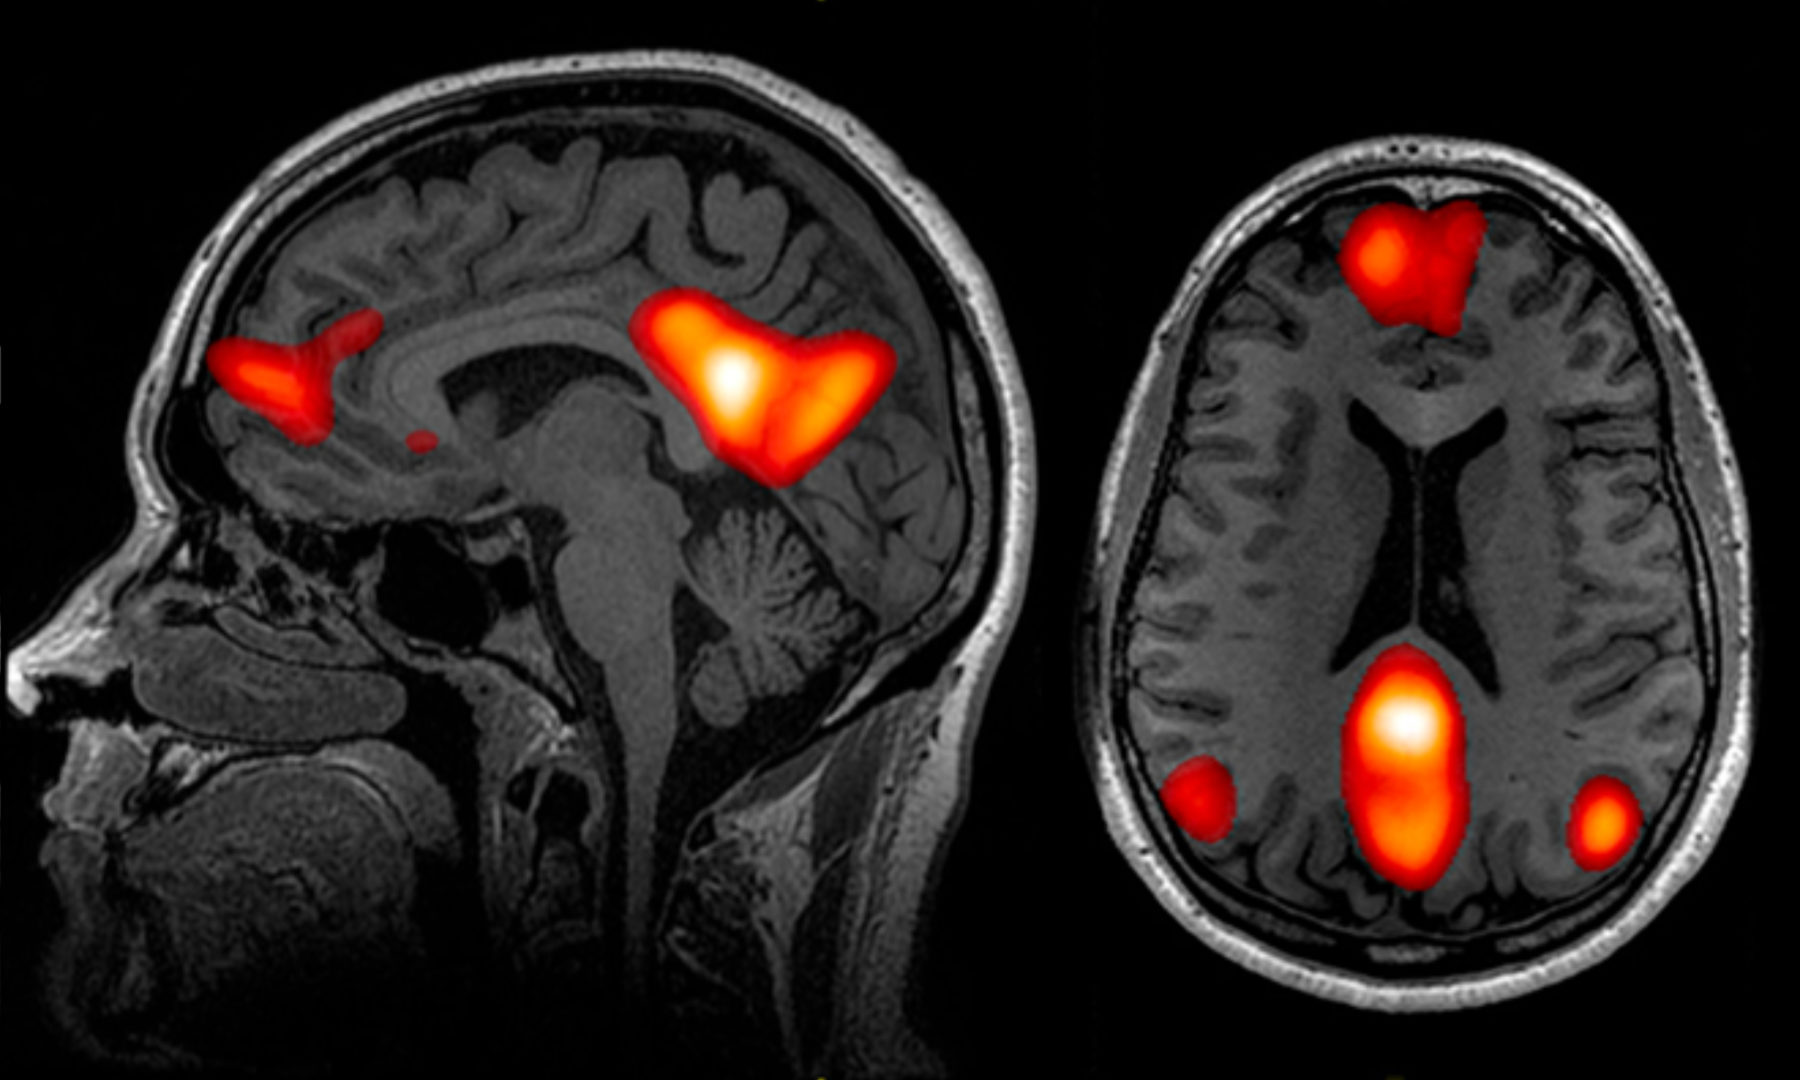

Was passiert, wenn 70 Forschungsteams aus aller Welt unabhängig voneinander denselben Datensatz analysieren, um dieselben Hypothesen zu prüfen? Diese Frage beantwortet erstmals eine internationale Studie, die von den Ökonomen Michael Kirchler, Jürgen Huber und Felix Holzmeister vom Institut für Banken und Finanzen der Universität Innsbruck mitinitiiert wurde. Gemeinsam mit Forschern des California Institute of Technology, der Stanford University, der Stockholm School of Economics und der Universität Tel Aviv haben sie rund 200 Wissenschaftlerinnen und Wissenschaftler eingeladen, den gleichen MRT-Datensatz zu analysieren und neun Forschungshypothesen zu überprüfen. Die Daten stammen aus einem Experiment in Tel Aviv, bei dem die Hirntätigkeit von 108 Probanden mit Hilfe von Funktioneller Magnetresonanztomographie aufgezeichnet wurde, während sie ökonomische Entscheidungen trafen. Das Verfahren zeigt mit hoher räumlicher Auflösung jene Hirnareale an, die während der Messung aktiv sind. Die neurowissenschaftlichen Forschungsteams wurden gebeten, diese Daten mit ihren etablierten Analyseverfahren dahingehend zu untersuchen, ob es Hinweise für einen Zusammenhang zwischen der Aktivität von Teilen des Gehirns und bestimmten Aspekten ökonomischer Entscheidungssituationen gibt.